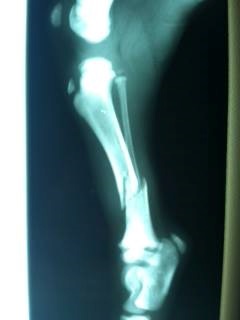

Not long after applying to foster through You Lucky Dog, I received a call asking if I would be willing to take on a challenging case. A young, female bully-mix pup named Dixie had been hit by a car and taken to a local animal hospital by the car’s driver. The caring staff at the hospital attempted to treat her injuries by putting both of her hind legs in casts. Unable to locate an owner for Dixie, the animal hospital reached out to local rescues for help. They were able to find a savior for Dixie in You Lucky Dog. Suspecting that Dixie’s injuries might need further medical care, she was taken to a partner vet for evaluation. It quickly became clear that Dixie’s situation was dire—she would need emergency surgery or risk losing her legs. Her right hind leg was most affected, and it could require amputation if corrective surgery was unsuccessful. Time was of the essence for this poor pup, and much depended on the skill of the doctors and staff charged with her care. After a challenging surgery, the doctor was hopeful that Dixie would regain her mobility and avoid amputation.

It was several days before Dixie was released from the hospital. These days were emotionally trying for me and my family. We were anxious to get Dixie into our home and begin the task of caring for her and helping her through her recovery to get her ready for her future forever home. The day finally came when Dixie was ready to come to our home, and I went to pick her up. It was one thing to have heard her story, but it was another thing entirely to see it. When I walked into that vet’s office, I saw a frail, emaciated young pup battered by neglect and life as a stray. Three of her legs were covered in protruding pins and needles that were literally holding her together. When she looked up at me, those eyes—oh those eyes. There was a world of hurt, betrayal, and confusion behind those eyes. As I gazed at her, those eyes told me her story over again, and I could literally feel the weight of all that this dog had been through sinking over me. At that moment, I welled up with an incredible sense of commitment and love. I owed it to Dixie to show her that there was so much more to life than what she’d seen so far.

Dixie’s road to recovery was not a simple one. For the first weeks in our home, she was in her kennel around the clock. One wrong move too early on in the recovery process, and she could easily reverse all the work that had been done to save her legs. She was a pitiful sight, huddled in her crate, unable to get away from all the uncomfortable, protruding metal pins that were providing the only hope for her future mobility. Our daily regimen included the tedious process of cleaning the rods and pins with Q-tips and peroxide and redressing her wounds. The rods would dig gashes into her shins, so I would carefully cover the tip of each one in surgical tape to protect her. This went on for several weeks, every day. It was a huge commitment, but I kept my thoughts on the ultimate reward of seeing her through to health and finding her forever home.

As I worked with Dixie each day, I could slowly see a glimpse of something new in her eyes. Little by little, she was learning to trust, and those beautiful eyes began to speak the words “thank you” as she realized she was in a safe and loving place. After several weeks, the doctors removed all of Dixie’s pins and rods. Though she was starting to look like a normal dog, her journey was far from over. Without the pins, we now had to keep our fingers crossed that her bones would begin to fuse properly. It was more important than ever that she stay calm and quiet in her crate as we waited patiently for her legs to heal.